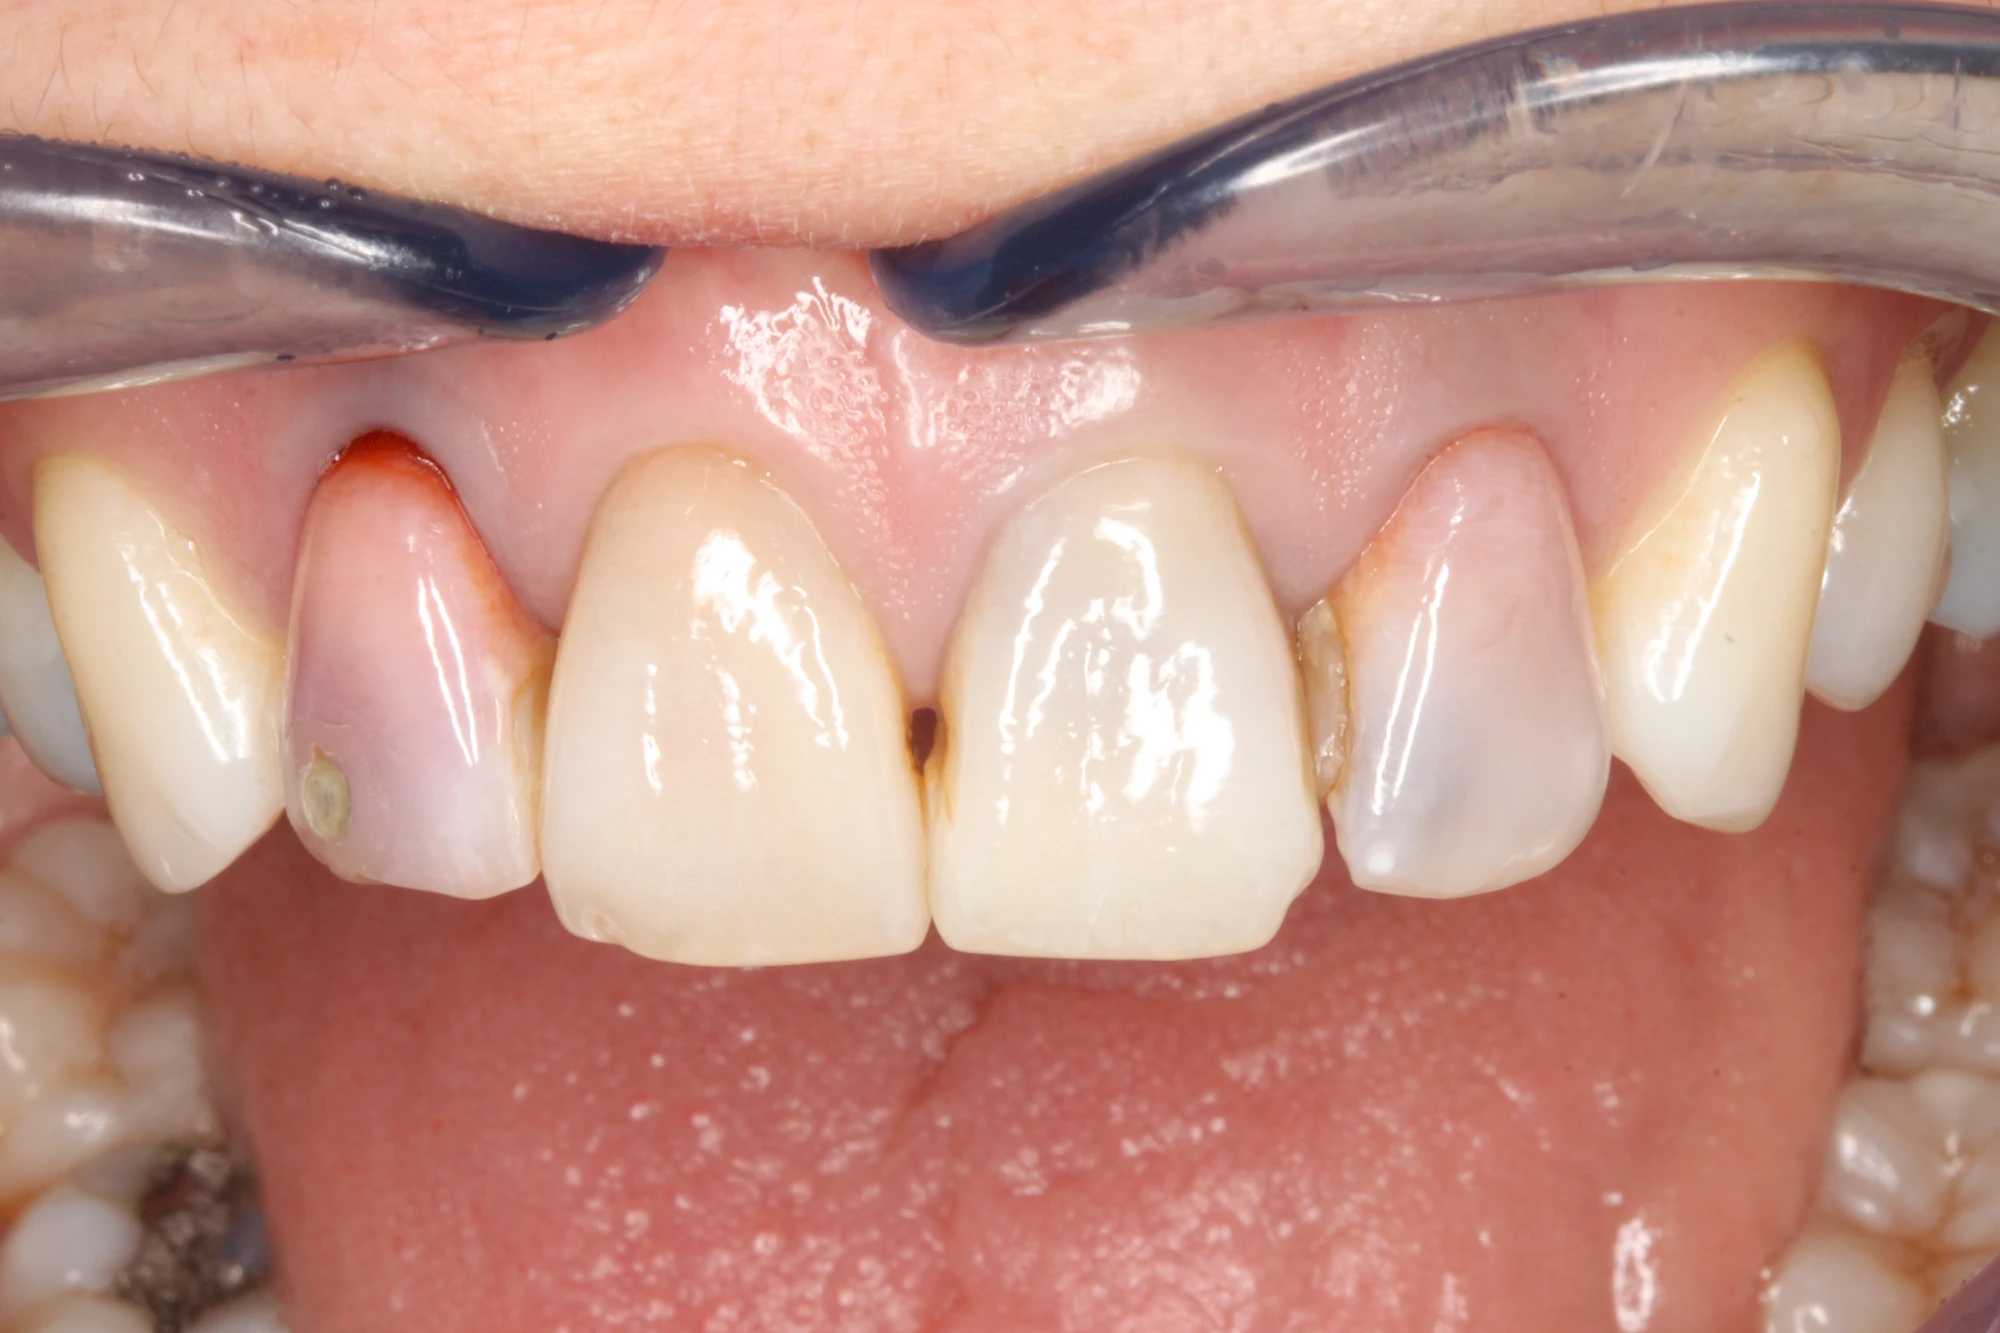

Bräunliche Verfärbung

Dunkle bzw. Rötliche Verfärbung

Ist ein einzelner Zahn deutlich dunkler als die Nachbarzähne kann das ein Zeichen sein, dass der Nerv abgestorben ist. Unter Umständen wurde bereits eine Wurzelkanalbehandlung vom Zahnarzt durchgeführt. Eine Abklärung durch den Zahnarzt ist in jedem Fall sinnvoll.